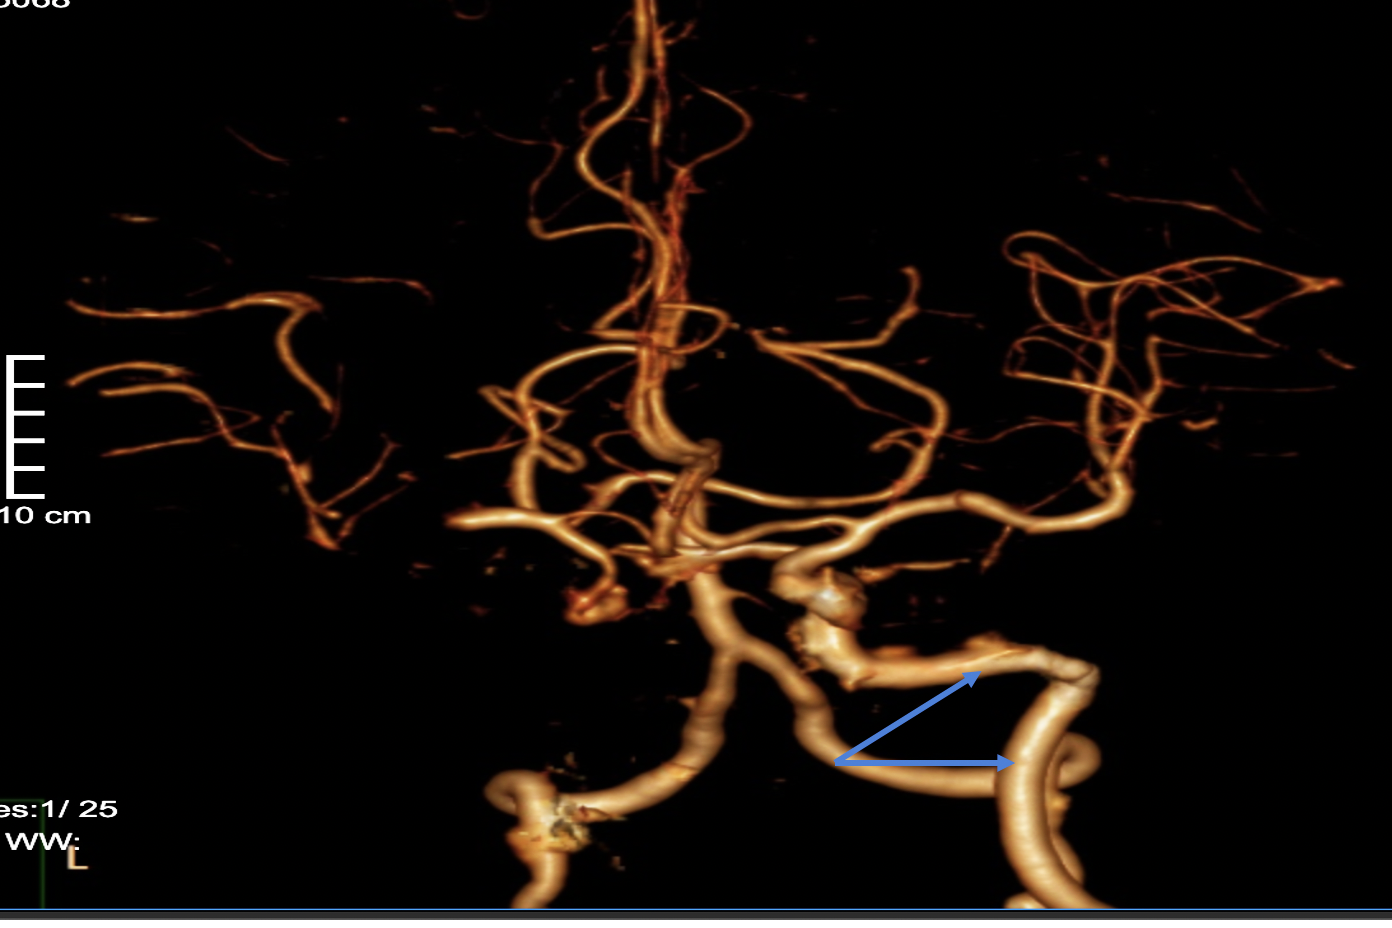

Dựa trên hình ảnh chụp cắt lớp mạch máu não, các bác sĩ phát hiện bệnh nhân từng có tình trạng hẹp động mạch cảnh trong trước đây nhưng không phát hiện, dẫn đến bị tắc cả động mạch cảnh trong bên phải và động mạch giữa não. Hội chẩn khẩn, ekip điều trị quyết định sẽ can thiệp mạch máu não cho bà H.

Bệnh nhân được chụp CT scan sọ não, ghi nhận không xuất huyết nhu mô não. Tiếp tục chụp CT mạch máu, người đàn ông được phát hiện tắc động mạch cảnh ở não.

Tại bệnh viện, qua chụp DSA, bệnh nhân được chẩn đoán bị tổn thương hẹp khít cuối động mạch cảnh. Ông P. được can thiệp nong bóng và đặt stent nội sọ, dùng các thuốc hạ mỡ máu, thuốc dự phòng huyết khối… Sau can thiệp, sức cơ dần phục hồi.